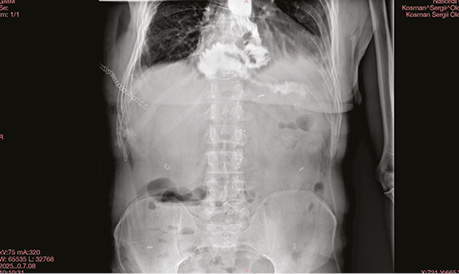

Обстеження та планування лікування. Лабораторні показники без клінічно значущих відхилень. Радіологічні дані, комп’ютерна томографія органів підтвердили наявність потовщення стінок нижньої третини стравоходу та кардіального відділу шлунка до 31 мм (рис. 1).

Рис. 1. Радіологічні дані локалізації первинної пухлини